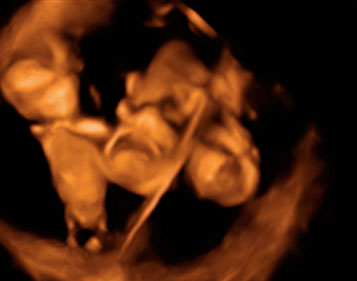

Ecografía 4D de semana 13: Bebé moviéndose

Es impactante ver los movimientos de este bebé de 13 semanas de gestación, que parece bailar en un escenario. En la ecografía 4D se aprecian perfectamente todas sus estructuras básicas (cabeza, tronco, extremidades...), incluso los genitales masculinos. Destaca la bipedestación de la figura -se encuentra erguida-, que parece más humana de lo que podríamos imaginar a esa edad gestacional.

Ecografía en 4D. Bebé de 13 semanas de gestación moviéndose

Tras ver esta ecografía, cuesta creer que este bebé tenga tan sólo 13 semanas de gestación. El bebé tiene unos movimientos muy humanizados a pesar de su corta edad gestacional.